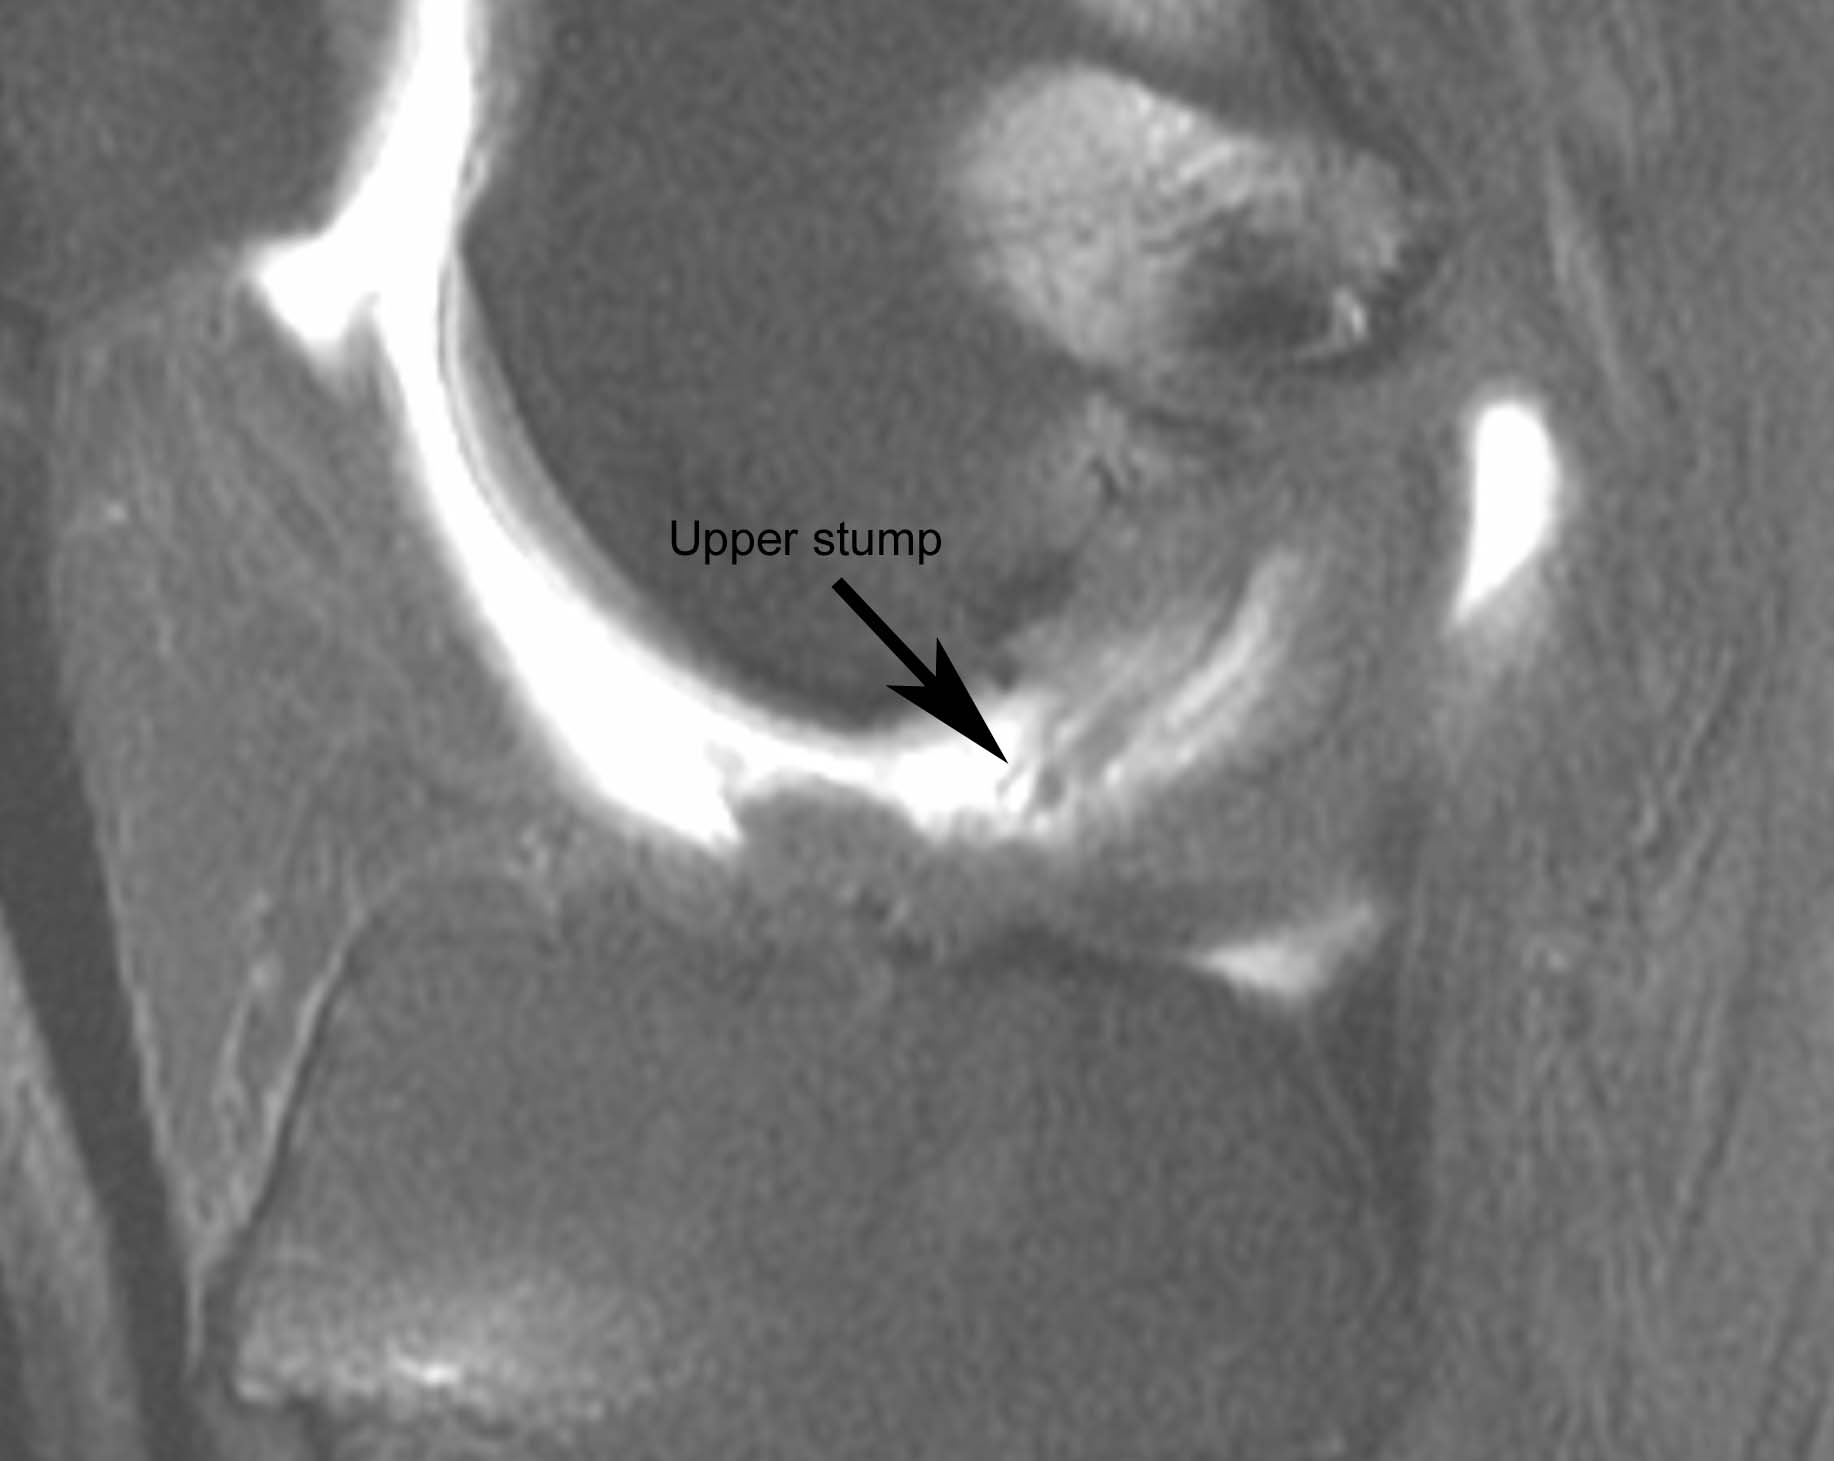

Figure 2 for case Disrupted ACL graft

Figure 2